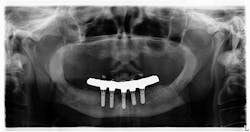

I typed in www.whatimplantisthat.com and was met with a page full of radiographic photos of implants—900-plus of them (figure 2). Wowza. I didn’t realize the full extent of the variety of implants out there. This, in and of itself, is fantastic. To begin your search, on the left side of the website, there is a list of filters that make the magic happen. What's even cooler is, if you can't figure it out on your own or are unsure of your diagnosis, you can pay to have someone help you.

Figure 2